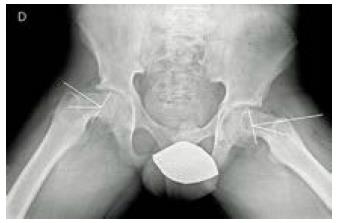

La radiografía comparativa anteroposterior (AP) y lateral de las caderas es fundamental en el abordaje de un paciente con cojera; específicamente en EFP existen hallazgos radiográficos que nos permiten orientar hacia un diagnóstico; en la proyección AP se puede visualizar una doble densidad radiográfica creada por la epífisis que se desplaza posteriormente y se superpone a la parte medial de la metáfisis conocida como el signo de Steel (Figura 2 B); También se puede apreciar un ensanchamiento relativo de la fisis (Figura 2 C) o una disminución de la altura de la epífisis (Figura 2 D). Finalmente, al trazar una línea en el borde superior del cuello femoral (línea de Klein), en una cadera normal esta debería cruzar la porción superior de la epífisis (Figura 2 A); en la EFP, esta línea no pasa por la epífisis o la cruza en menor grado que en la cadera sana (Signo de Trethowan) (Figura 2 E) 1,9,15,17,18.

La EFP también puede clasificarse radiológicamente según el porcentaje de desplazamiento de la cabeza femoral respecto al cuello, siendo leve cuando el desplazamiento es menor al 33 %, moderado cuando el desplazamiento está entre el 33 % y el 50 % y severo si tenemos un desplazamiento mayor al 50 % (Figura 3). El otro método de clasificación es el descrito por Southwick, el cual depende de la magnitud del ángulo epifisariometafisario en la proyección lateral; este se obtiene trazando una lin ea paralela al cartílago de crecimiento de la cabeza femoral. Se dibuja una perpendicular a esta linea y luego se traza una linea que sigue el eje del cuello femoral. El angulo formado por estas dos últimas líneas determina el grado de desplazamiento comparándose con la cadera sana, y puede clasificarse como leve cuando el angulo es menor a 30 °; moderado, si el angulo esta entre 30 ° y 50 °; y grave, cuando es mayor a 50 ° (Figura 4) 15,17.